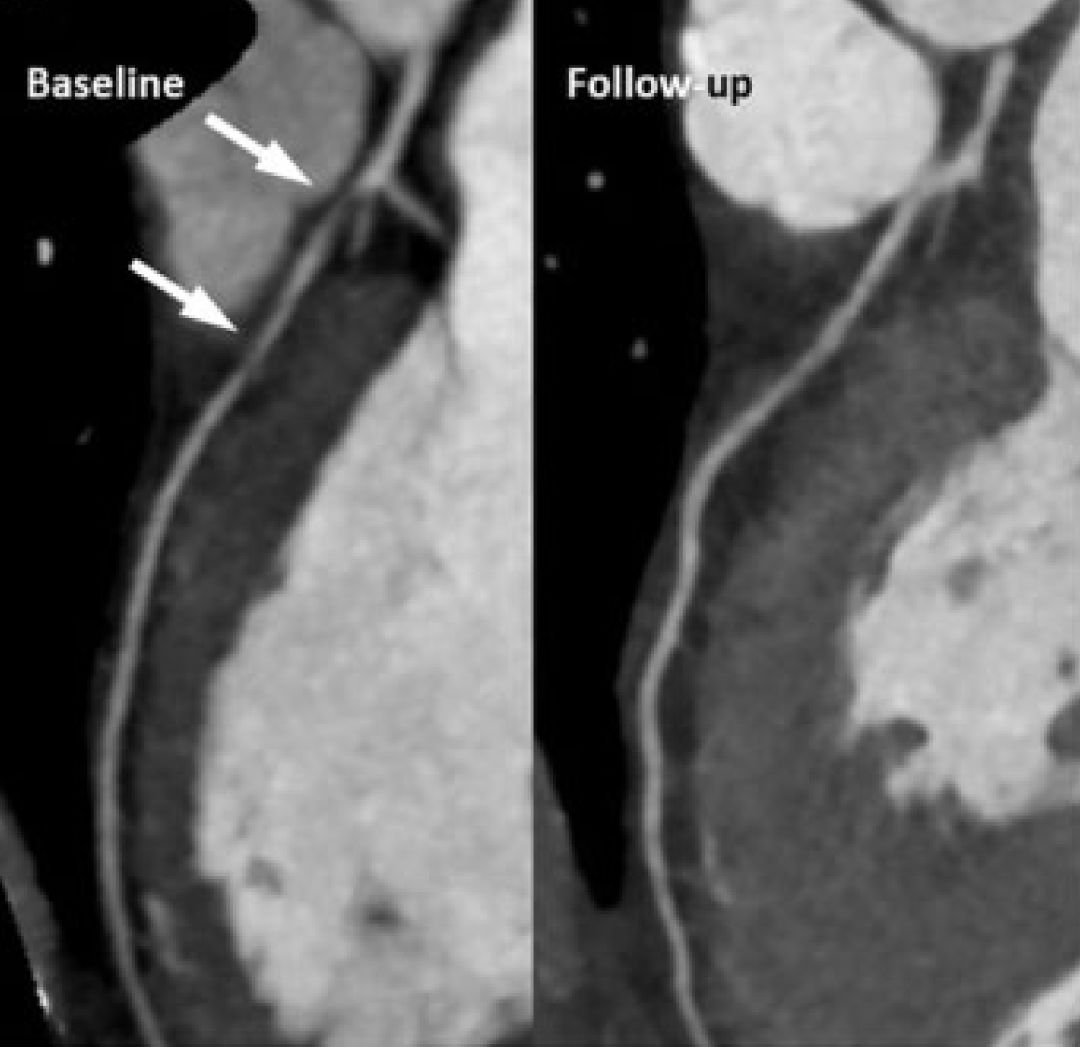

一位没有明确心血管危险因素的44岁中年女性,因“劳力性心绞痛2个月”就诊。为患者行冠脉CTA检查,发现LAD近端存在非钙化斑块,狭窄约70%,之后行核素检查确认LAD下游缺血。于是进行了冠脉造影,在LAD近端存在弥漫性中度狭窄,FFR为0.73。IVUS显示左主干与前降支弥漫斑块、负性重塑,最小管腔面积3mm2,斑块负荷55%。因为病变特点及患者个人意愿,并未进行介入治疗,维持了阿司匹林、地尔硫䓬、依折麦布+辛伐他汀治疗。

3年后为患者复查,惊奇地发现患者LAD下游缺血消失,行冠脉CTA显示斑块已经完全消退。

图1 LAD斑块完全消失